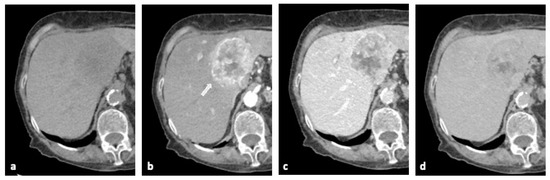

2.2. Computed Tomography (CT)